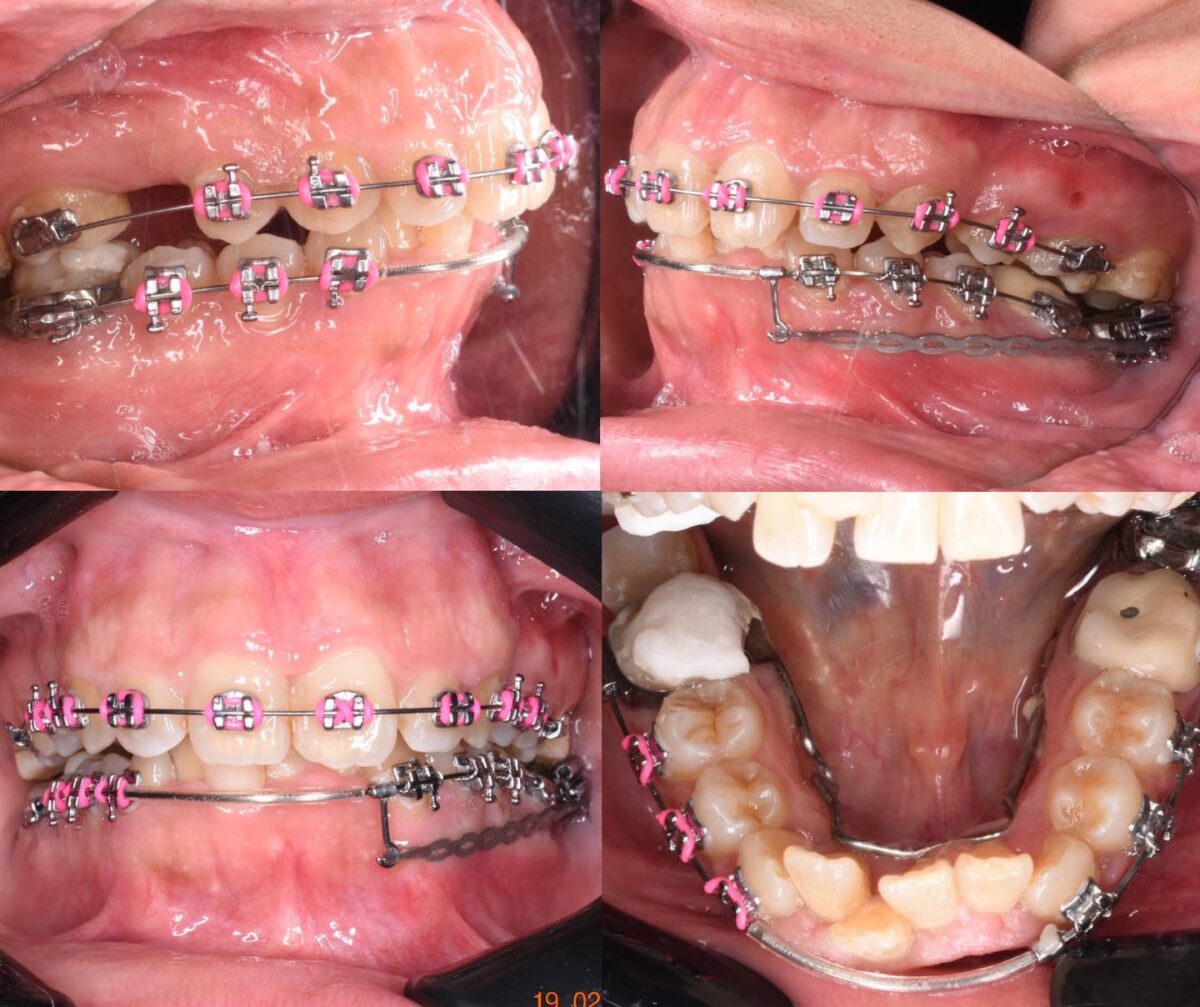

للي محتاجين تقويم، سواء معدني أو شفاف، العيادة بتوفر أحدث حلول التقويم المناسبة لكل حالة، مع متابعة دورية لضمان تقدم العلاج بالشكل المطلوب. وكمان لو في فقدان سن، بيتم تعويضه بزرعات أسنان من التيتانيوم المعتمد دوليًا بعد فحص شامل لعظام الفك وأشعة دقيقة، لضمان أفضل ثبات ونتيجة تدوم سنين.